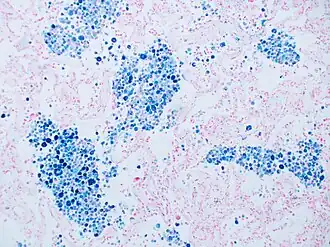

Stain for iron

Prussian blue is a common histopathology stain used by pathologists to detect the presence of iron in biopsy specimens, such as in bone marrow samples. The original stain formula, known historically (1867) as "Perls Prussian blue" after its inventor, German pathologist Max Perls (1843–1881), used separate solutions of potassium ferrocyanide and acid to stain tissue (these are now used combined, just before staining). Iron deposits in tissue then form the purple Prussian blue dye in place, and are visualized as blue or purple deposits.[54]